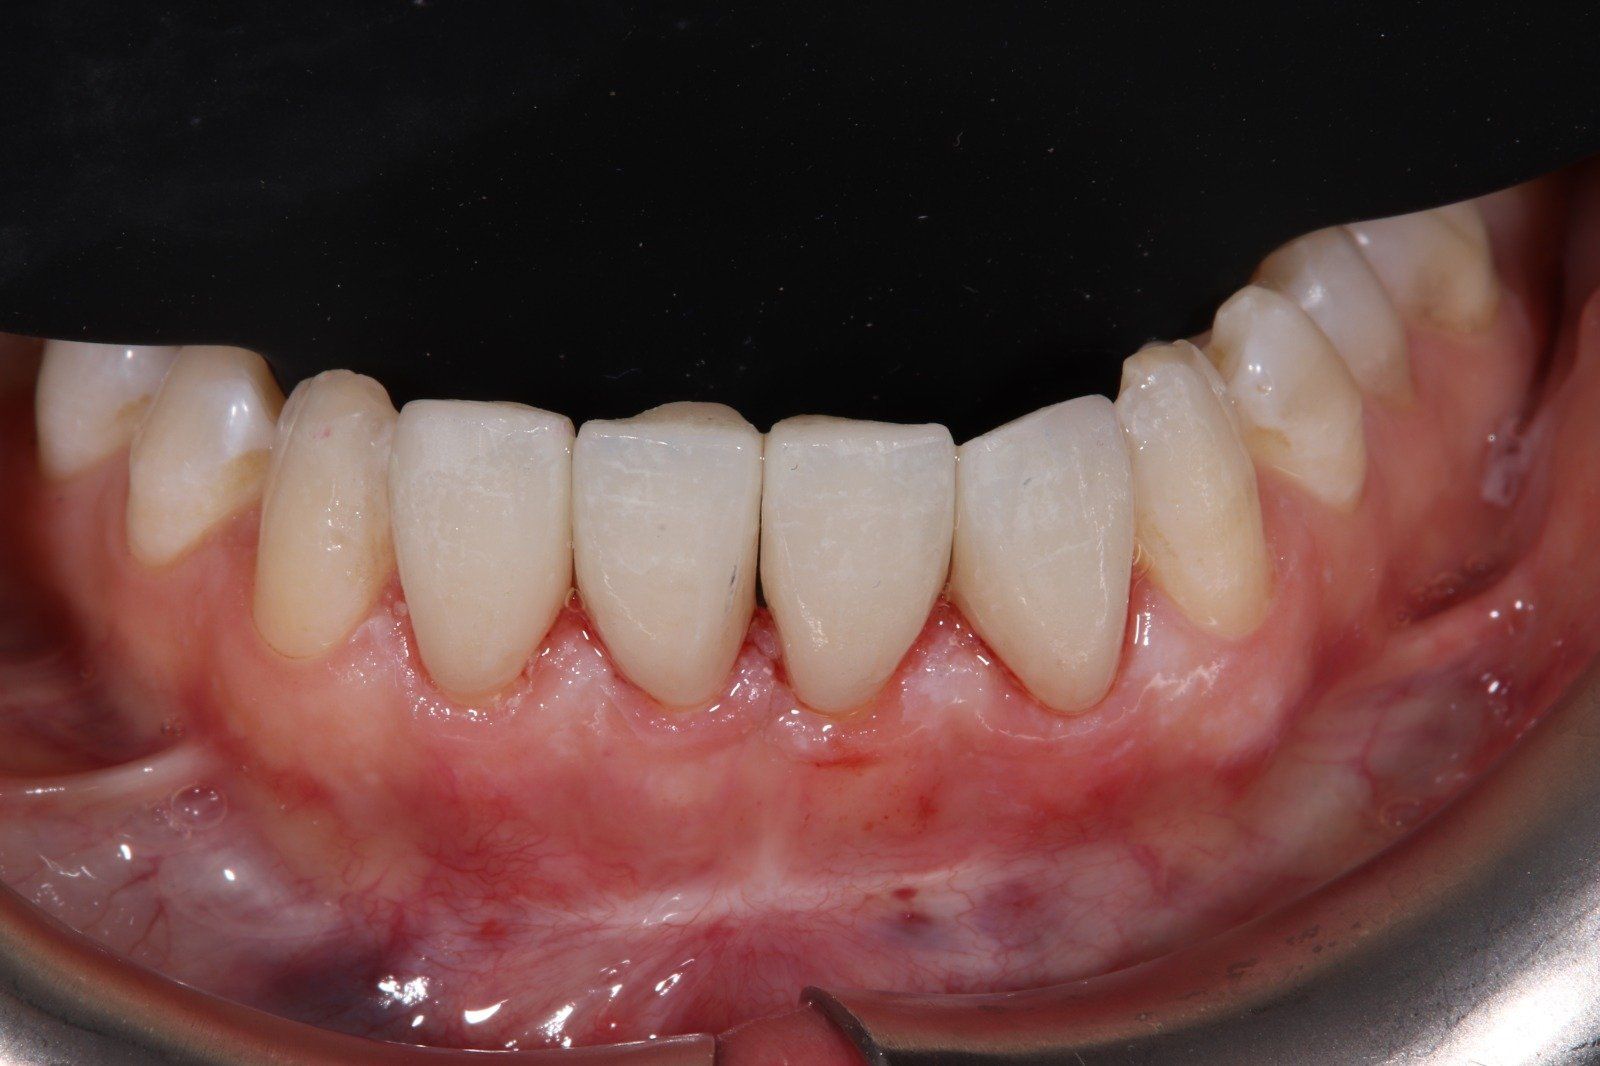

CASOS DE CARILLAS DE CERÁMICA

En Estildental hemos realizado muchos tratamientos de odontología estética y carillas de cerámica en todos estos años. Aquí le presentamos un caso de carillas de cerámica reciente: